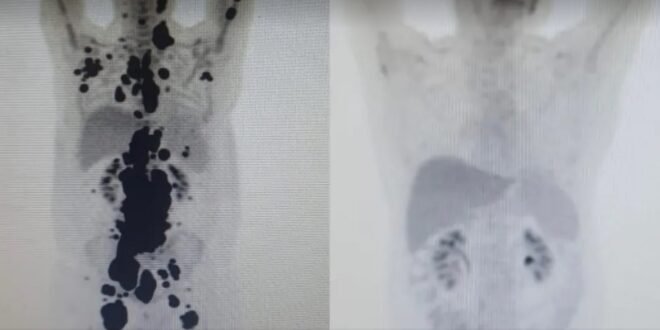

“A vitória não é só minha. É da fé, da ciência e da energia positiva das pessoas. Cada uma delas ajudou a colocar um paralelepípedo nesse caminho. A imagem prova com muita clareza para qualquer pessoa a gravidade do meu linfoma, e eu não tinha ideia de que era assim”, contou o paciente.

“Foi uma resposta muito rápida e com tanto tumor. Fico até emocionado [ao ver as duas ressonâncias de Paulo]. Fiquei muito surpreso de ver a resposta, porque a gente tem que esperar pelo menos um mês depois da infusão da célula. Quando a gente viu, todo mundo vibrou. Coloquei no grupo de professores titulares da USP e todo mundo impressionado de ver a resposta que ele teve”, comemorou o especialista.

Antes e depois

As duas imagens do Pet Scan (tomografia feita com um contraste especial) (veja acima) representam “dois Paulos”: a da esquerda, o paciente que tinha como caminho único os cuidados paliativos, quando a alternativa é dar conforto, mas já sem expectativa de cura, e a da direita, um paciente com um organismo já sem tumores após o tratamento com CAR-T Cell.